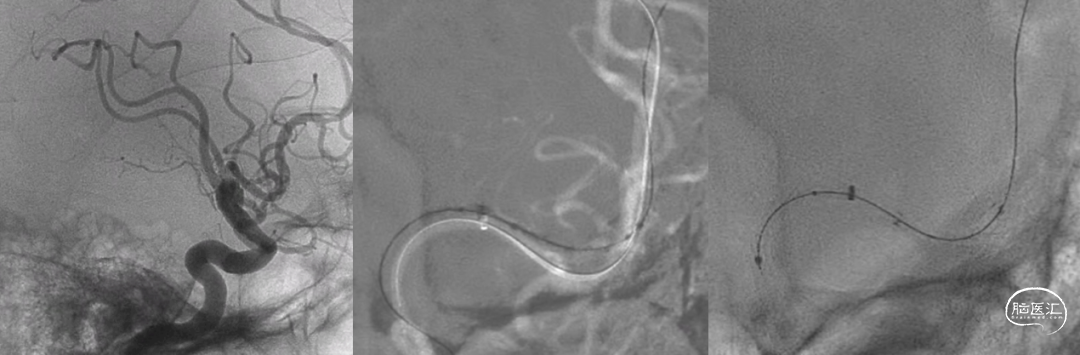

8F指引勾选左侧颈内动脉,推送Sofia导管至左侧大脑中动脉闭塞段近端;Sofia导管抽除少量团块样血栓,闭塞段血运复通,责任病变段血管重度狭窄。

Synchro-14微导丝留置于左侧大脑中动脉下干远端分支建立轨道;沿导丝送入加奇SacSpeed® 2mm×9mm颅内球囊,造影定位于狭窄段。

加奇SacSpeed® 2mm×9mm颅内球囊缓慢充盈成形扩张原位狭窄段;经球扩后,责任病变血管狭窄程度明显改善,前向血运流速改善。

责任病变血管管壁毛糙,内膜撕裂?血栓附壁?